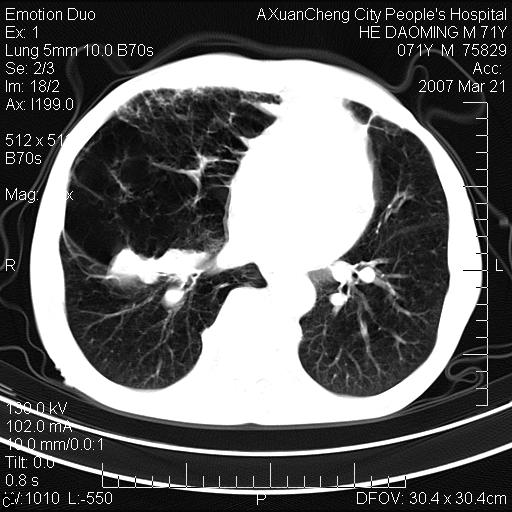

标题: CT7269:[原创] 咳嗽,咳痰,大家讨论右肺病变的部位 [打印本页]

标题: CT7269:[原创] 咳嗽,咳痰,大家讨论右肺病变的部位

1.慢支肺气肿 肺心病 肺大泡;2.叶间裂积液,前胸膜粘连

右侧相当于叶间软组织样密度ct值约50hu,请大家讨论是什么性者病变

考虑:慢性支气管炎合并全小型肺气肿、肺大泡、间质纤维化、感染,右斜裂积液。

慢性支气管炎,全小叶性肺气肿,右肺上.中叶肺大泡,伴有感染.支气管扩张.

考虑慢支,肺气肿,肺大泡,间质纤维化;右侧斜裂液气胸考虑(可能因为肺大泡破裂破入斜裂所致).

考虑病变以右上中肺多发肺大泡为主并感染。请结合临床考虑慢支肺气肿,肺心病。

1双肺慢性支气管炎并全小叶型肺气肿肺大泡2间质性纤维化3右侧斜裂积液

考虑:慢性支气管炎合并右侧全小型肺气肿、肺大泡并感染、双肺间质纤维化,右斜裂积液。

如果患者变化一下体位扫描可分辨液平与斜裂的关系。